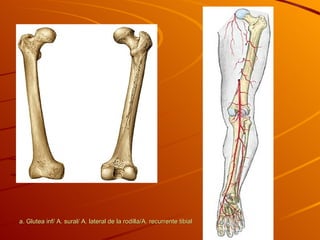

a. Glutea inf/ A. sural/ A. lateral de la rodilla/A. recurrente tibial

a. Glutea inf/A. sural/ A. lateral de la rodilla/A. recurrente tibial

• #13 a. Glutea inf/ A. sural/ A. lateral de la rodilla/A. recurrente tibial